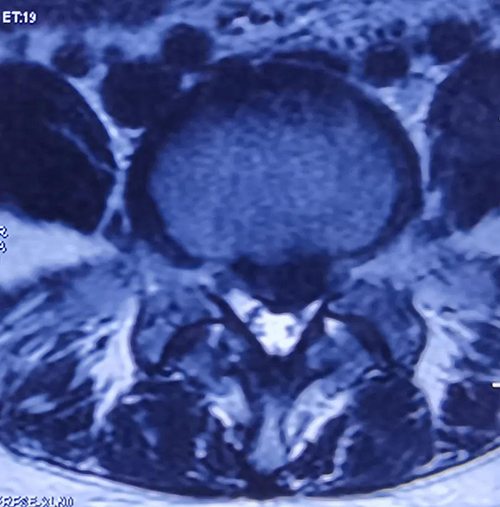

术中透视定位L4/5内镜位置